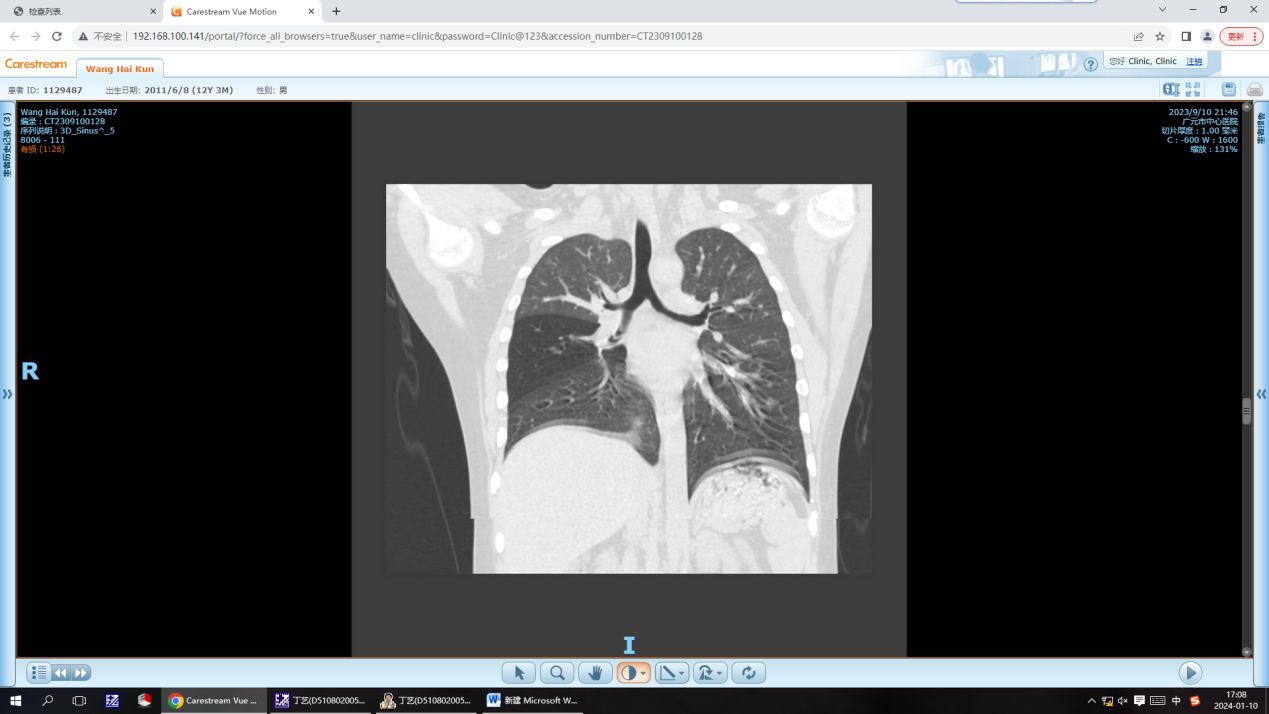

案例三:家住朝天的王同学,今年12岁了,因持续“咳嗽、喘息”开始被诊断为肺炎,在外院已经输液治疗了8天,但效果欠佳,故转入广元市中心医院继续治疗。在医院住院期间,儿二科丁艺医生详细询问了孩子的病史,结合查体,觉得他不是单纯的喘息性疾病,反复询问孩子家属,曾经是否有异物呛咳史,孩子爸爸仔细回忆后告诉我们,3个月前孩子玩中性笔时曾经有过异物呛咳史,但孩子告诉他早都从肚子里拉出去了。丁医生将信将疑,觉得还是得给孩子做一个胸部CT排除一下异物卡入气道的可能性,结果一做就发现了大问题。CT显示患儿右中间支气管—右下支气管开口处管壳样稍高密度影。这些信息都提示患儿有气管支气管异物的可能,针对目前情况,最佳处理方法就是行支气管镜检查+异物取出术。于是儿童气道异物团队马上分工协作,成功将异物取出。